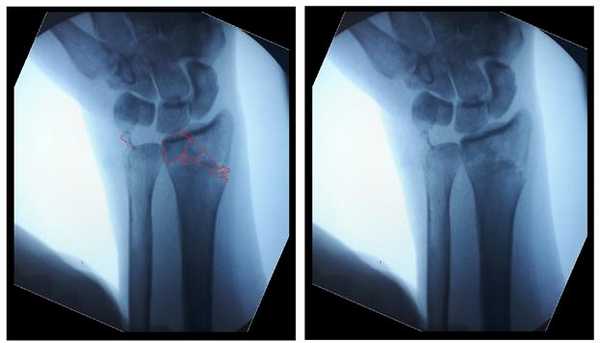

Интраоперационно под контролем ЭОП произведена закрытая репозиция перелома.

После репозиции на рентгенограммах отчётливо виден многоооскольчатый, нестабильный характер перелома.

Произведён доступ к месту перелома по ладонной поверхности предплечья. При ревизии выявлено множество мелких осколков в метафизарной области по волярному кортексу. Произведена открытая репозиция перелома, временная фиксация спицами. Накостно уложена пластина VA-LCP™ Two-Column Distal Radius Plate

После рентгенконтроля производится введение блокируемых винтов диаметром 2,4 или 2,7 мм.

Данная пластина отлично подходит для фиксации оскольчатых переломов дистального метаэпифиза лучевой кости, однако в ряде случаев, когда перелом располагается более дистально, предпочтительнее использовать пластину другой конструкции (Volar rim).

Окончательный остеосинтез после проведения всех винтов выглядит на рентгенограмме примерно так. На левой части рисунка схематично отображено расположение фрагментов кости, фиксированных пластиной.